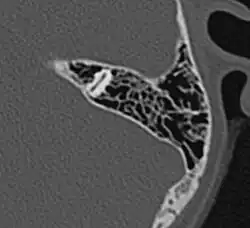

Развитие пневматизации околоносовых пазух и ячеек сосцевидных отростков достигается мешковидным выпячиванием слизистой оболочки полости носа и среднего уха в компактное вещество кости. Окончательное развитие околоносовых пазух у человека достигается к 20—25 годам. Некоторые животные не имеют воздухоносных костей (тюлени, киты), у некоторых объём пневматизации, напротив, выше, чем у человека. Развитие пневматизации височной кости завершается к пяти-шести годам; наиболее выражена пневматизация ячеек сосцевидных отростков. Размеры ячеек различаются; так, у некоторых индивидуумов сосцевидный отросток остаётся практически не пневматизированным, что, вероятно, обусловлено предшествующими частыми воспалительными процессами в среднем ухе; у других, напротив, пневматизированные ячейки могут распространяться в чешуйчатую часть височной кости, скуловой отросток или к вершине пирамиды.